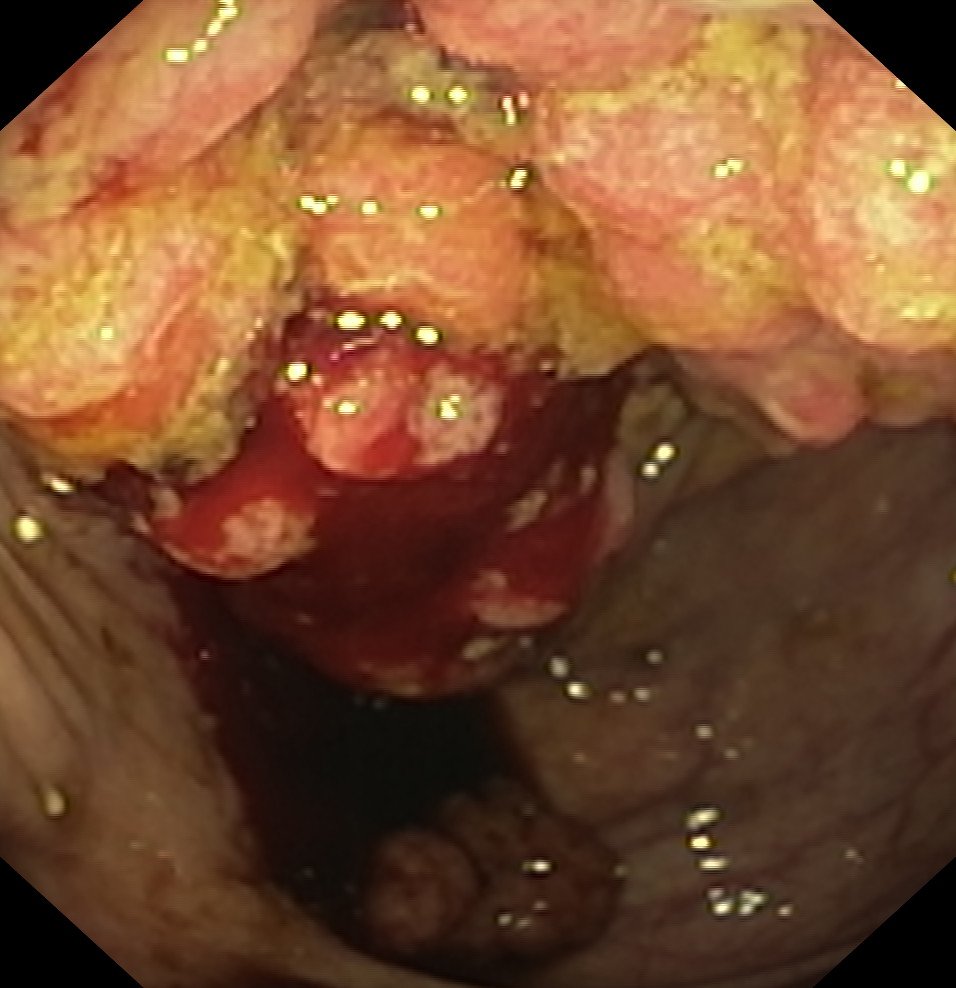

Obrazy endoskopowe

Nowotwory przewodu pokarmowego